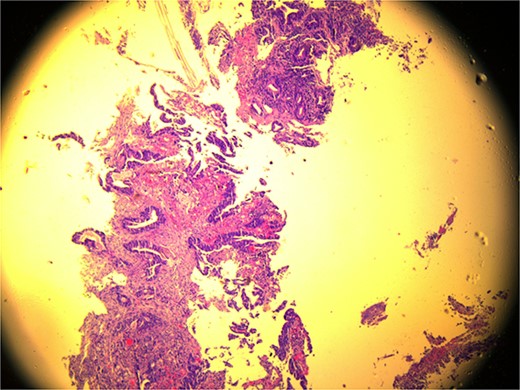

A 59-year-old female patient, married with no offspring. Surgical history includes cholecystectomy (2017). Her brother died due to lymphoma; otherwise, there is no family history of cancer. She presented complaining of chronic constipation, weight loss, abdominal distention, and perianal pain. Colonoscopy revealed a 5-cm mass extended from the anus. Biopsy revealed invasive, moderately differentiated rectal adenocarcinoma (Fig. 1).

Microscopic view (×10) of pathology slide of colorectal cancer.